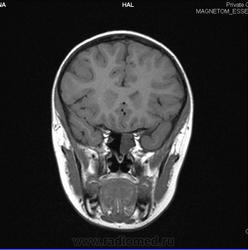

Терапию мы провели, но зрение продолжало сильно падать (за год от -1 до -3,5), поля зрения выпадали. Сделали МРТ повторно (приложено, Ссылка на файлы http://files.mail.ru/7MT6OM , ссылка на фото http://files.mail.ru/7MT6OM?t=1 . После скачивания: Показать в папке / Открыть с помощью / Программа просмотра изобр. и факсов или Paint, или Microsoft Office Picture Manager и т.д.).

Вновь никаких неврологических нарушений, и вновь обнаружили сфеноидит и аденоиды 2-3 ст. Но основная пазуха теперь уже заполнена почти полностью. Никаких других симптомов (головной боли, выделений, температуры и проч.) нет. Поэтому некоторые ЛОР -врачи считают, что падение зрения может не связано с сфеноидитом.

Серию всю не скачал, но глядя на картинки сложилось впечатление о выраженном неравномерном утолщении слизистой, содержимого гнойного или слизистого внутри пазухи не увидел, но надо смотреть серию DICOM. Утолщена слизистая в одной из ячеек решетчатой кости справа.

процесс в основной пазухе описал бы как мукоцеле,связи по мрт картинкам нет !необходимо исключить  демиелинизирующий процесс ,исключить надо синдром Девика,сделать исследование спинного мозга ,если даже результаты будут отрицательными делать исследование через каждые 3 месяца с контрастом обязательно,сделать исследование цереброспинальной жидкости на олигоклональные антитела

Ну что, был отек слизистой, а потом прошел. Вряд ли причина ухудшения зрения была в сфеноидите, нужно искать другую причину.

Мукоцеле, кстати, не было. Был отек слизистой оболочки с субтотальным (а не тотальным) нарушением пневматизации пазухи.